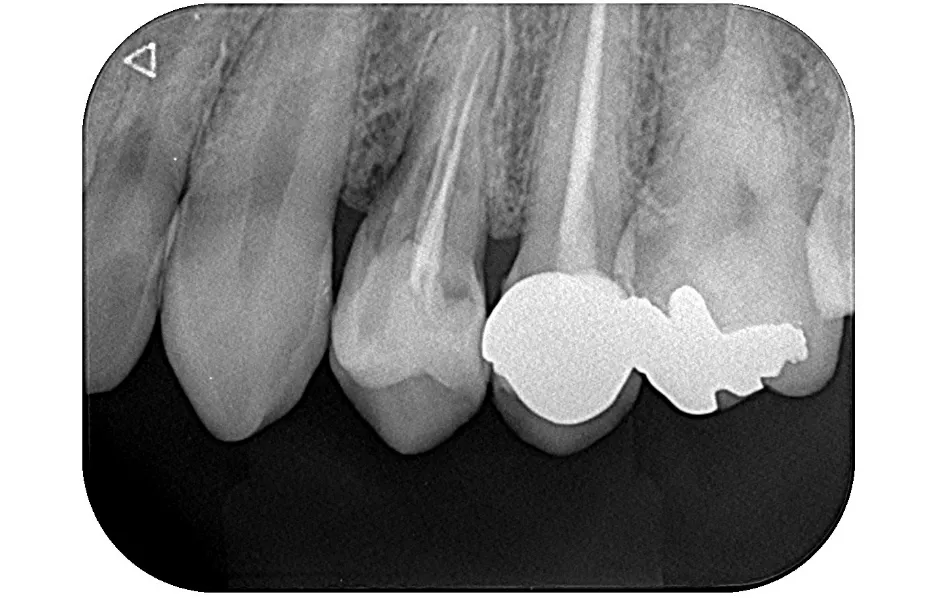

精密根管治療

神経まで進行して炎症を起こしている虫歯に対して行なう治療法になります。感染した神経を取り除き、しっかりと洗浄・消毒し、最後に薬剤を詰めて被せ物を装着します。

精密根管治療 -